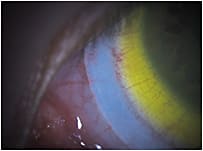

Asymmetric Blanching Another conjunctival blanching pattern observed in scleral lens wearers is asymmetric or non-uniform blanching (Figure 2). In these cases, the area of excessive blanching or bearing is usually perpendicular to areas of edge lift or alignment due to the anatomical shape of the eye.

Figure 2. An example of non-uniform scleral lens edge blanching, typically at 3 o’clock and 9 o’clock. This patient would benefit from a toric haptic system.